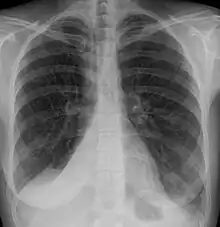

Atelectasis of a person's right lung

Clinically significant atelectasis is generally visible on chest X-ray; findings can include lung opacification and/or loss of lung volume. Post-surgical atelectasis will be bibasal in pattern. Chest CT or bronchoscopy may be necessary if the cause of atelectasis is not clinically apparent. Direct signs of atelectasis include displacement of interlobar fissures and mobile structures within the thorax, overinflation of the unaffected ipsilateral lobe or contralateral lung, and opacification of the collapsed lobe. In addition to clinically significant findings on chest X-rays, patients may present with indirect signs and symptoms such as elevation of the diaphragm, shifting of the trachea, heart and mediastinum; displacement of the hilus and shifting granulomas.[10]